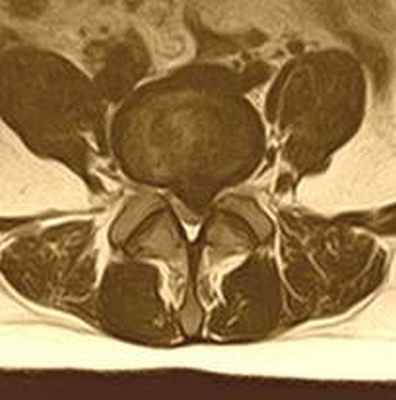

| Медианная грыжа межпозвонкового диска - редкое расположение грыжевого выпячивания, практически всегда - на уровне L5-S1. При большом размере грыжи диска операция выполняется обязательно - для предупреждения нарушения функции тазовых органов. | ![]() |

![]() | Парамедианная грыжа диска - самый часто встречающийся тип грыжи диска, среди пациентов, попадающих к хирургу, когда грыжевой мешок выпячивается в проекции манжетки корешка (самое болезненное место у нерва), а также вызывает компрессию дурального мешка и проходящих в нем нескольких нервных корешков, что смазывает классическую неврологическую картину заболевания. Пациенты с такими грыжами могут достаточно долго - порой до полугода - с переменным успехом лечиться у невролога, пока не попадут на консультацию к нейрохирургу, и, испытав долгий период постоянной боли, - приходят к выводу о неизбежности операции. при этом в послеоперационном периоде многие сожалеют, что так долго терпели, и не знали о том, что операция на позвоночнике - это легкий и быстрый путь жить без боли |

| Латеральная грыжа межпозвонкового диска - второй по частоте вариант расположения грыжи диска, когда хрящ прорывает все связки позвоночника и занимает положение в латеральном кармане - наиболее узком месте у входа нервного корешка в просвет позвоночного канала. Как правило, обычные обезболивающие никогда не снимают полностью боли в ноге при таком расположении грыжи диска. Пациенты, быстро испробовав на себе различные варианты терапии, как только узнают об истинной причине болей - быстро соглашаются на операцию на позвоночнике. | ![]() |

![]() | Фораминальная грыжа диска - редкий тип грыж диска, может сочетаться с истмическим спондилолизом, который в свою очередь дагностируется при спиральной компьютерной томографии. Сложен в диагностике, так как в просвете позвоночного канала грыжи не находят, но боли очень сильные. В этом случае небольшая - 3-4мм грыжа диска располагается в самом узком месте - фораминальном отверстии, где совсем небольшой кусочек хряща может сильно зажать нервный корешок. Лечение исключительно хирургическое. |